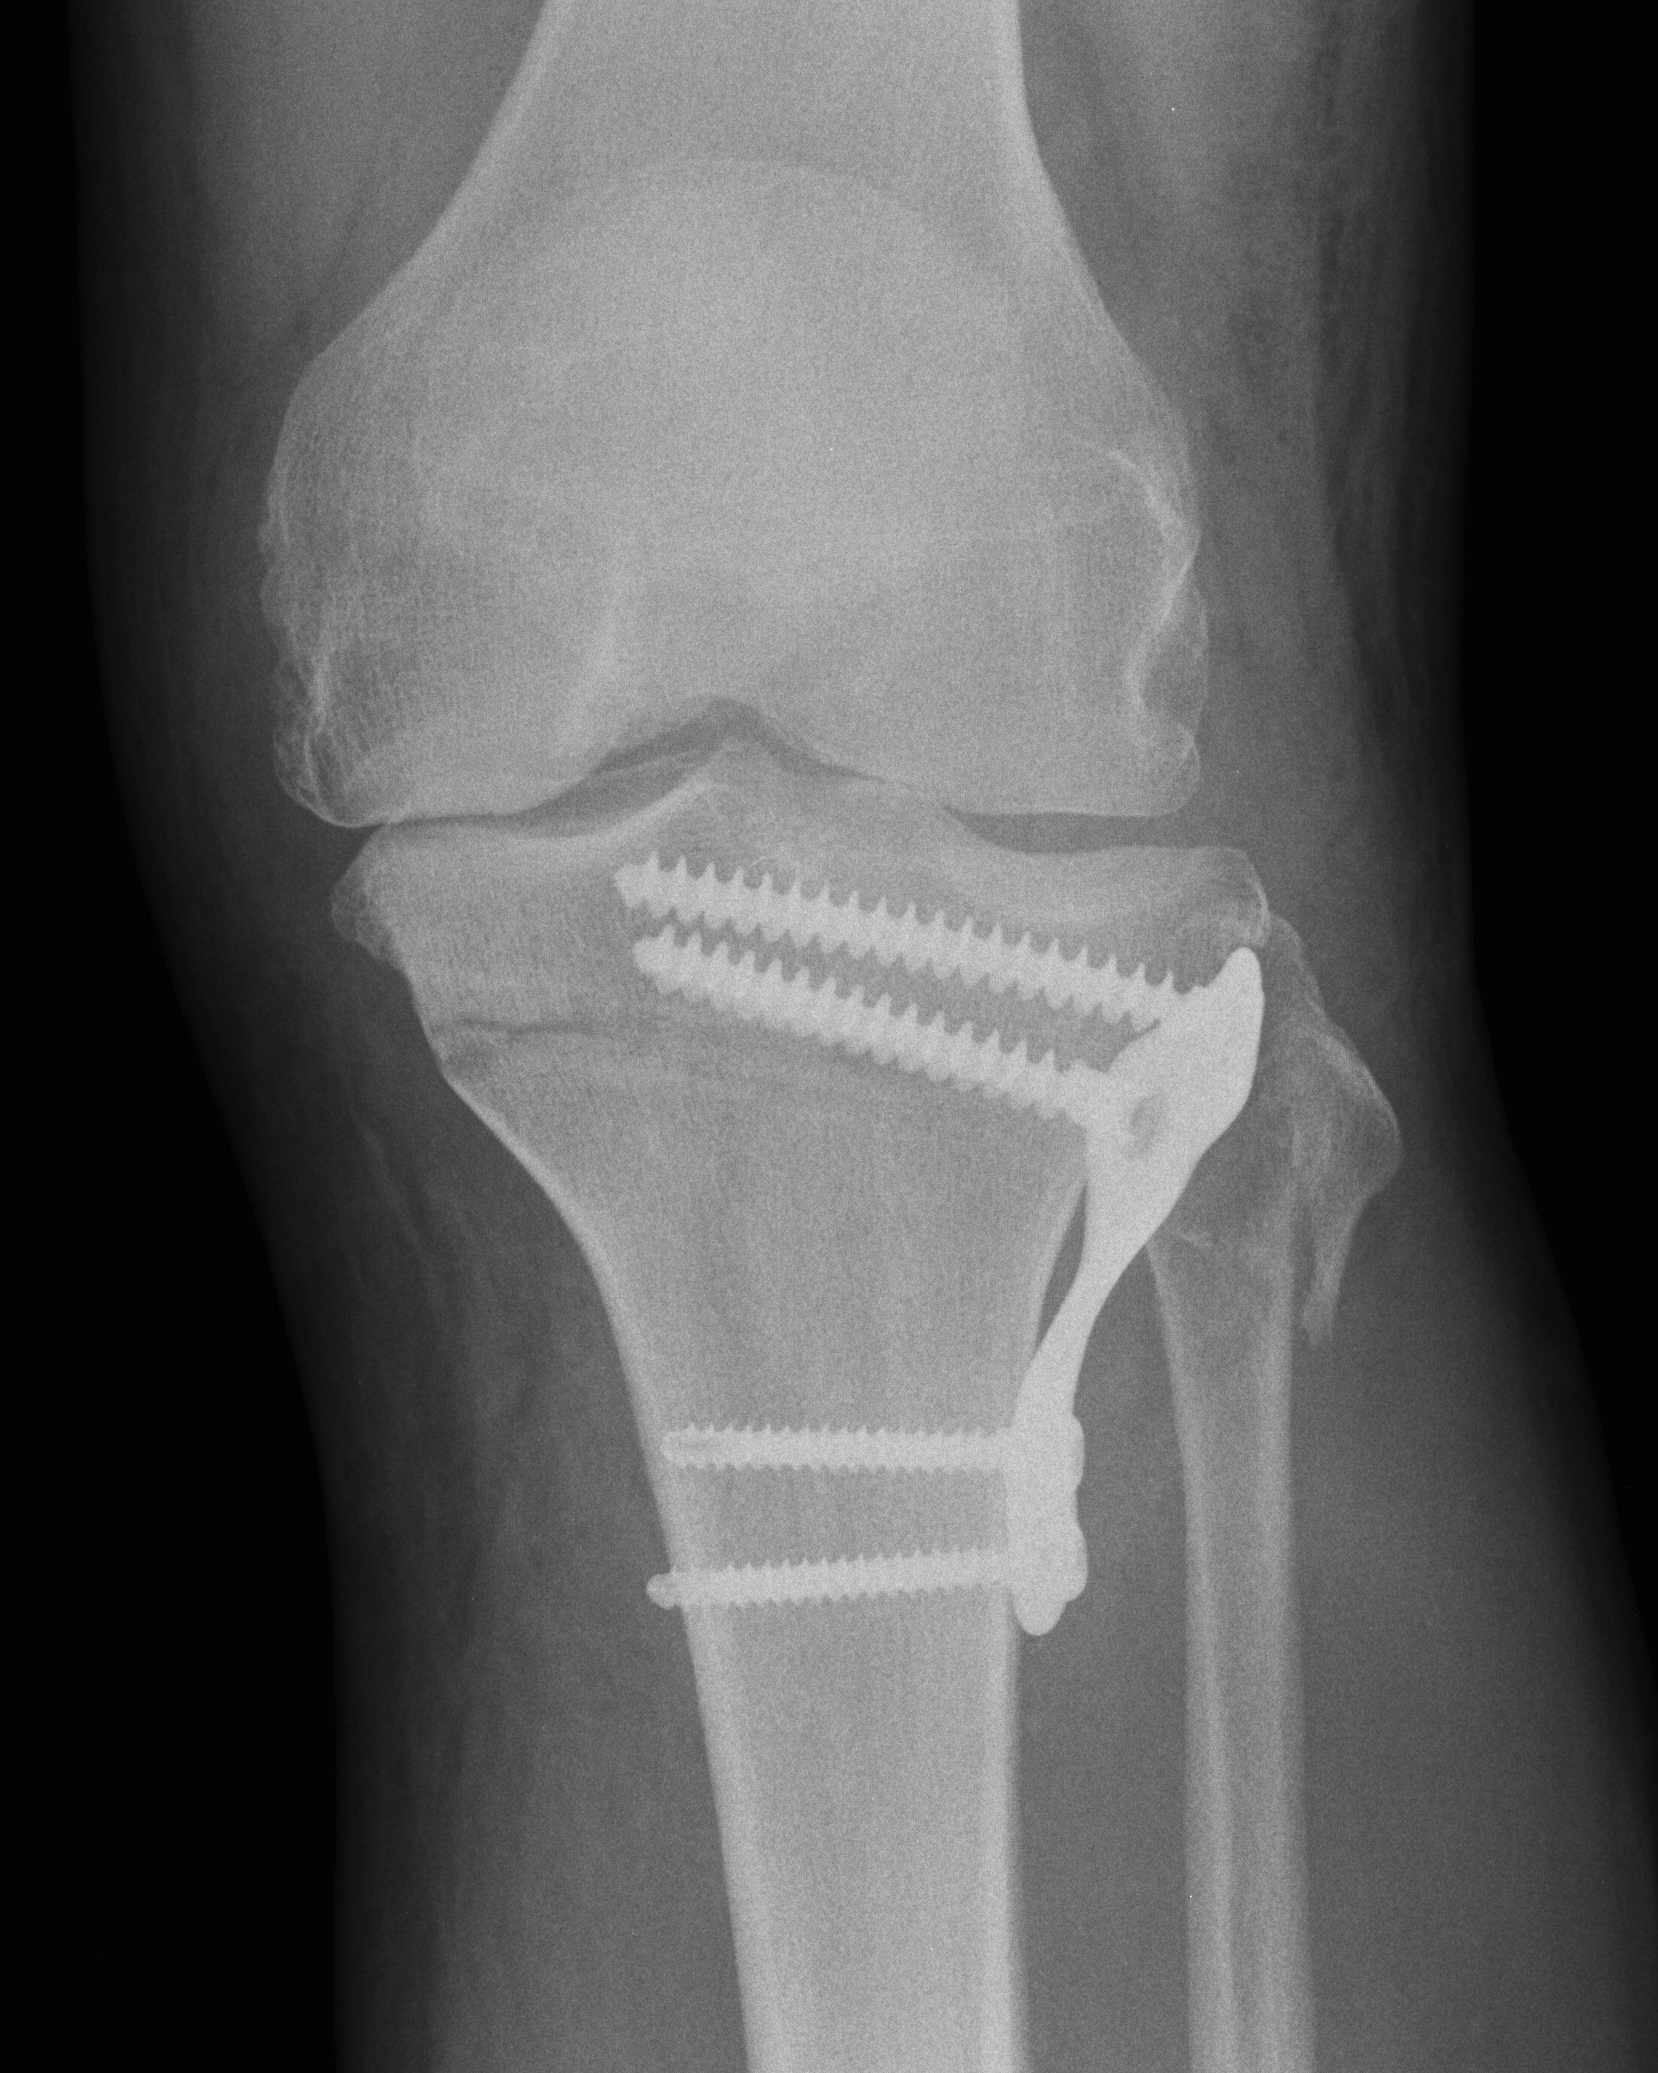

Preoperative Calculations

Calculate Desired Correction on Long Leg Views

1. Simple Calculations

Measure anatomic femoral tibial angle

- normally 5-8o

Calculate correction desired

- need to overcorrect to 8o femoro-tibial alignment

- or correct to mechanical axis of 180o